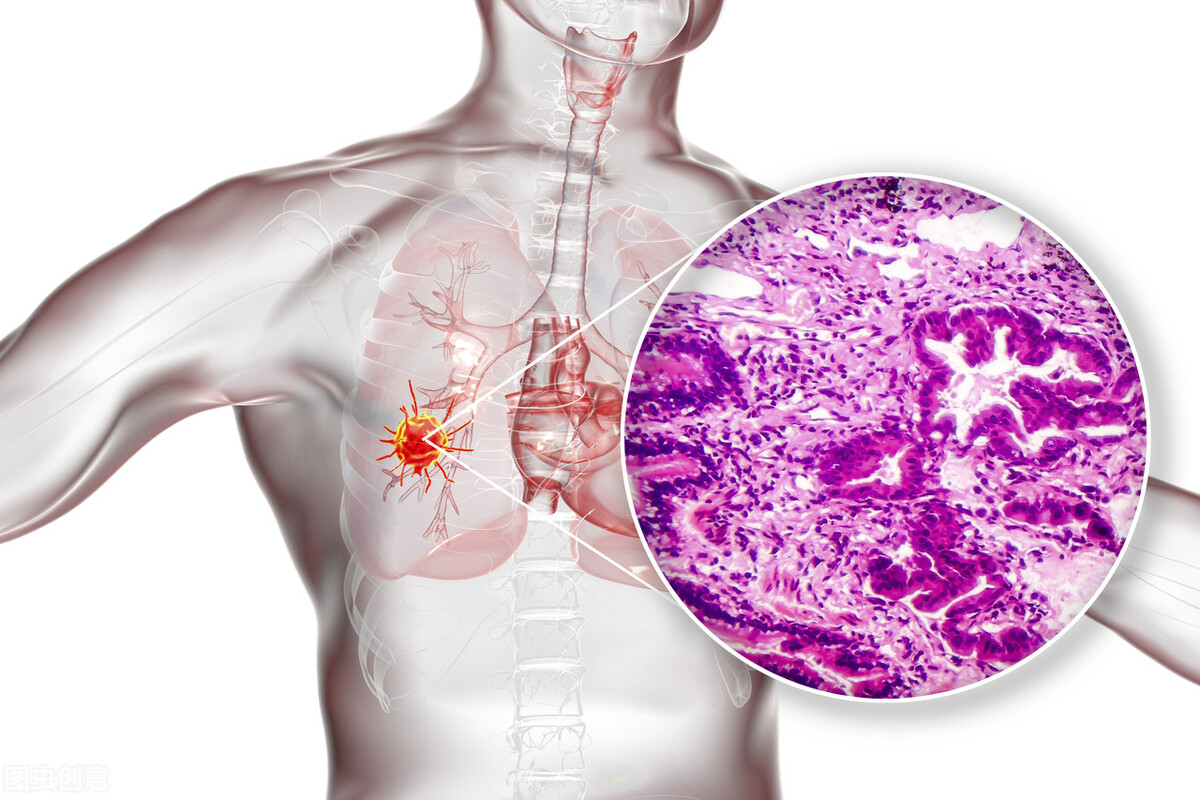

A45精准靶向治疗小细胞肺癌是比较新的一种治疗肺癌的方法,对于小细胞肺癌有很好的治疗的作用,它属于一种精准的靶向性治疗,在彻底清除癌细胞方面的作用是比较好的,同时还不会损伤人体的其他的组织和器官,在激发患者身体免疫力方面也有很好的效果,能够降低转移的概率。